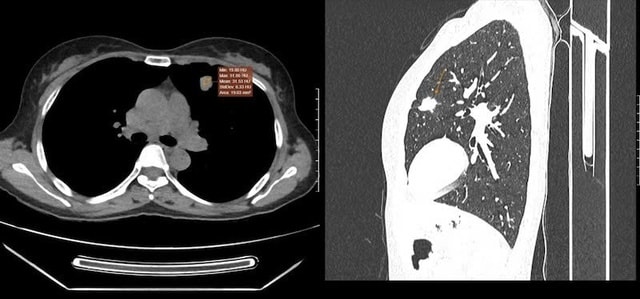

Tuy nhiên, hình ảnh chụp cắt lớp vi tính (CT) lồng ngực có tiêm thuốc cản quang lại cho thấy nốt đặc kích thước 21x14mm với bờ tua gai tại thùy trên phổi trái, đồng thời phát hiện thêm nốt giảm tỷ trọng tại tuyến thượng thận.

Để xác định bản chất tổn thương, các bác sĩ tiến hành sinh thiết xuyên thành ngực dưới hướng dẫn của CT, mẫu bệnh phẩm gửi đến Trung tâm Giải phẫu bệnh MEDLATEC cho kết quả ung thư biểu mô tuyến.